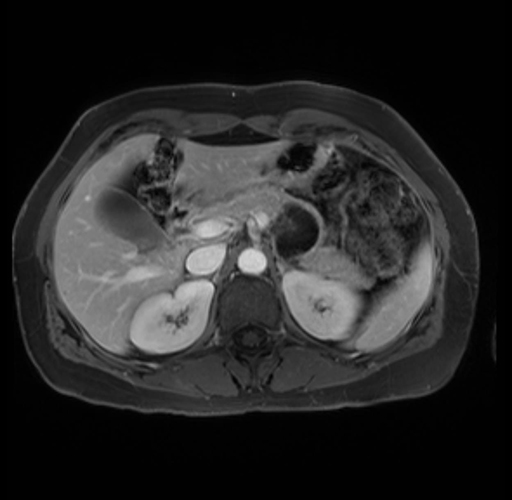

Imaging Analysis

Look through the patient's CT scan to identify any areas of concern for the necessary procedure.

Based on your CT findings, which issue(s) are present and would give reason for "planned slowing down moment(s)" in this case?